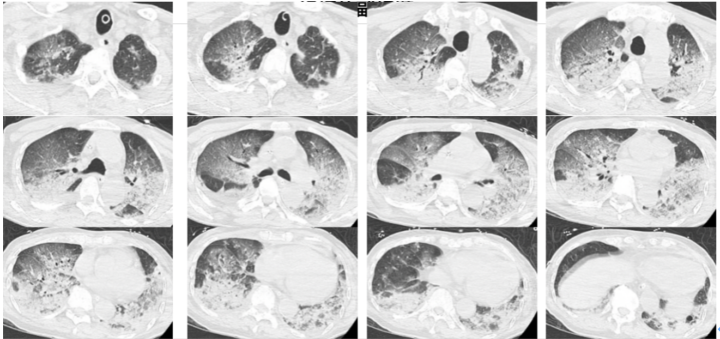

医生接诊后一度怀疑韩爷爷有肺栓塞或脑梗。此时的韩爷爷意识不清,血压下降、心率也降到30次/分,氧饱和度在80%~90%之间,急查血气显示pH仅有7.094,二氧化碳分压高达77.4mmHg,有明显的II型呼衰和呼吸性酸中毒。医生立即启动抢救程序,韩爷爷插管后被送到CT室进行了头颅、胸部CT和肺血管CTA检查。‍‍检查结果显示,韩爷爷的两肺全“白”了。

过了四天,韩爷爷的病情基本稳定,再次进行CT检查后发现有明显改善。入院第六天,韩爷爷的呼吸机撤机,气管插管拔除,从ICU转入呼吸科普通病房。入院第10天,第三次CT检查显示,韩爷爷的双肺已基本正常。